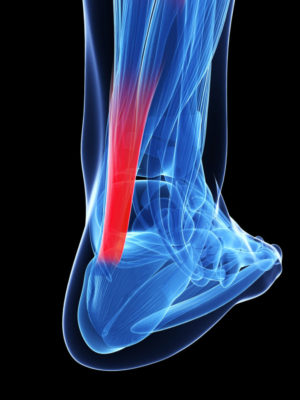

As we mentioned yesterday during our breakdown of Kirk Cousins’ Achilles tendon tear, this week on the blog has been deemed “Achilles Week.” We are going to spend the week looking at a number of different aspects of Achilles tendon tears and their management. Today, we’re going to explore some of the risk factors that can increase an athlete’s likelihood of a partial or complete Achilles tendon rupture.

As we mentioned yesterday during our breakdown of Kirk Cousins’ Achilles tendon tear, this week on the blog has been deemed “Achilles Week.” We are going to spend the week looking at a number of different aspects of Achilles tendon tears and their management. Today, we’re going to explore some of the risk factors that can increase an athlete’s likelihood of a partial or complete Achilles tendon rupture.

Achilles Tendon Rupture Risk Factors

An athlete’s Achilles tendon rupture risk profile is an intricate interplay of numerous factors. While some of these elements are within our grasp to manage, there are others that remain beyond our control. We encourage you to proactively address the controllable factors while maintaining an awareness of those elusive elements. Here’s a glimpse into the factors that shape your risk profile for an Achilles tendon tear: